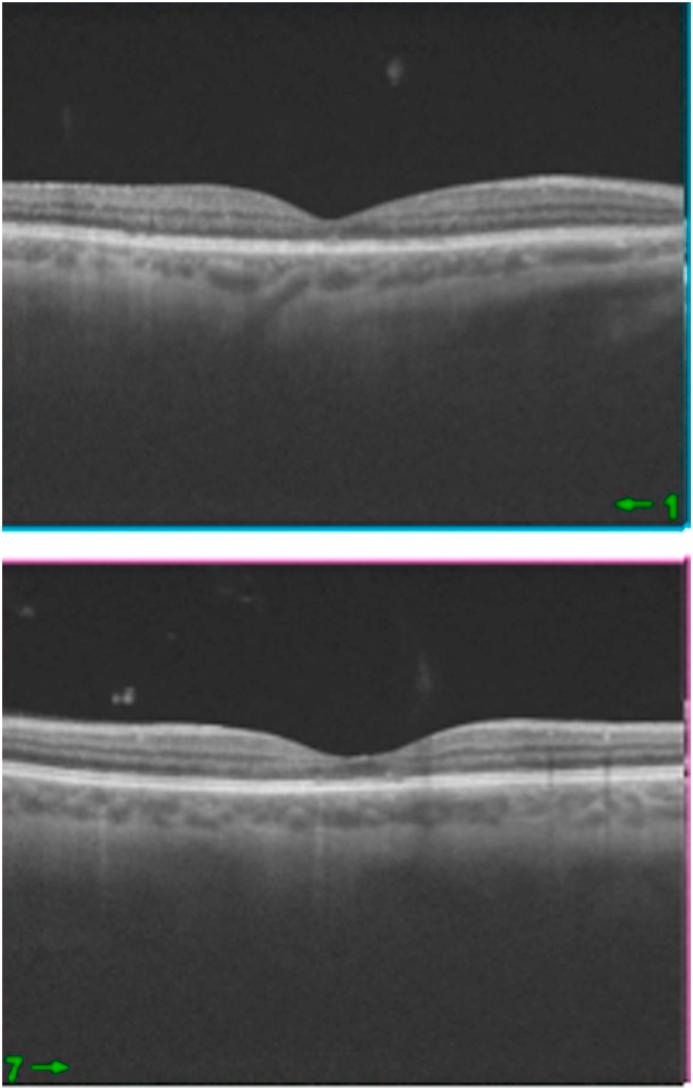

A 46-year-old man underwent a technically uneventful right eye phacoemulsification surgery using a standard dose (1mg/0.1mL) of cefuroxime solution injected into the anterior chamber at the end of the surgery. Serous macular edema and detachment were in our case observed on the first post-operative day. Without surgical intervention fast clinical recovery was observed and best corrected visual acuity improved to the final visual outcome of 1.0, which was satisfactory 10 days after surgery.

一名46岁男性接受了右眼白内障超声乳化手术,手术技术上顺利,在手术结束时向前房注射了标准剂量(1mg/0.1mL)的头孢呋辛溶液。在术后第一天观察到我们病例中的浆液性黄斑水肿和脱离。未经手术干预,观察到临床快速恢复,最佳矫正视力提高到最终视力1.0,术后10天效果满意。